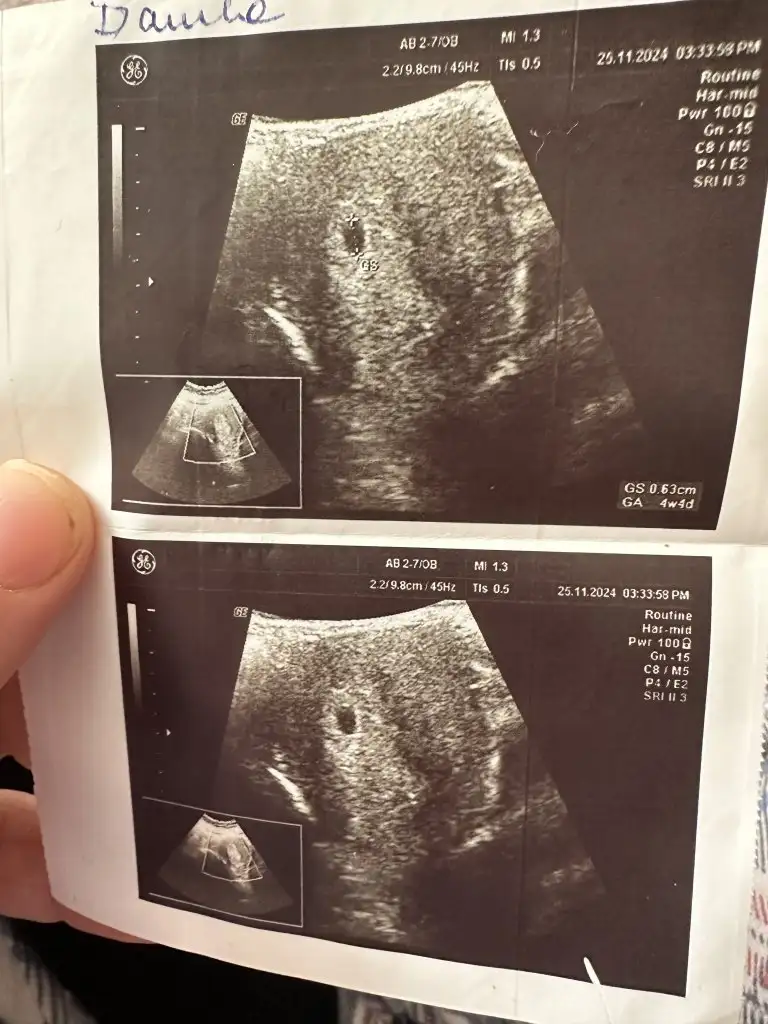

4hafta4gunluk kese gordum kalp ıcın beklıyorum kese 3bın olunca gorunuyor benım 3600düKızlar keseyi ne zaman gördünüz? Kalp atışını ne zaman duydunuz? 4+5’teyim şu an

Keseyle birlikte bebeği de görmüş müydünüz4hafta4gunluk kese gordum kalp ıcın beklıyorum kese 3bın olunca gorunuyor benım 3600dü

Keseyi 4+4 te gördük alttan ultrasonla ama bebek yok cuma günü tekrar gidicem tam 6 haftalık oluyor insallah görürüz bu sefer cok korkuyorum boş gebelik olmasından birbirimize dua edelimKızlar keseyi ne zaman gördünüz? Kalp atışını ne zaman duydunuz? 4+5’teyim şu an

4+5 de kese 6+0 da kalp atışı duydukKızlar keseyi ne zaman gördünüz? Kalp atışını ne zaman duydunuz? 4+5’teyim şu an